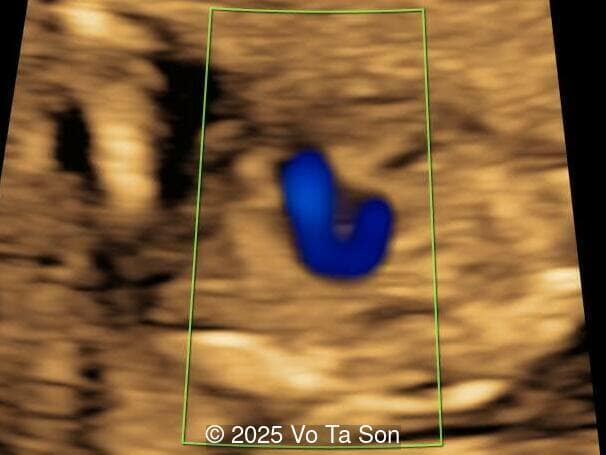

A woman underwent routine prenatal screening at 13 weeks. The non-invasive prenatal test (NIPT) showed low risk for common aneuploidies including trisomy 21, 18, and 13. However, first-trimester anomaly scan revealed multiple fetal anomalies.

Please describe the abnormalities and provide a syndromic diagnosis that best fits the presentation.